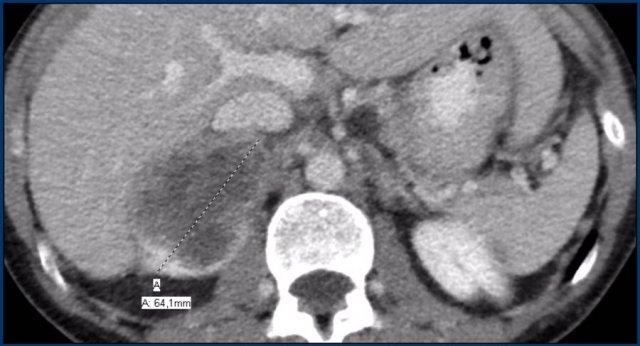

Tổn thương không xác định > 4 cm

Đường kính lớn nhất của khối tuyến thượng thận có giá trị tiên lượng ác tính.

Đặc biệt, các tổn thương > 4 cm có khả năng cao là di căn hoặc ung thư biểu mô vỏ thượng thận.

Kích thước khối tuyến thượng thận còn quan trọng vì hai lý do khác.

Tiên lượng chung tốt hơn đối với ung thư biểu mô vỏ thượng thận kích thước nhỏ, và các khối u nhỏ hơn cũng dễ cắt bỏ hơn bằng các kỹ thuật phẫu thuật xâm lấn tối thiểu.

Do đó, khuyến cáo đối với khối tuyến thượng thận không xác định có kích thước > 4 cm và không có tiền sử ung thư là phẫu thuật cắt bỏ – trong hầu hết các trường hợp không cần sinh thiết – nhằm điều trị kịp thời ung thư biểu mô vỏ thượng thận nguyên phát có thể xảy ra [3,9].

Các trường hợp tiếp theo là ví dụ về các tổn thương không xác định > 4 cm.

Tất cả đều được phát hiện tình cờ ở những bệnh nhân không có tiền sử ung thư.

Tất cả các chẩn đoán đều được xác nhận bằng mô bệnh học và cho thấy sự đa dạng của cả khối u lành tính lẫn ác tính.

Hình ảnh cho thấy một khối không đồng nhất, bờ không rõ, kích thước lớn hơn 4 cm.

Có vùng trung tâm ngấm thuốc kém, nhiều khả năng là do hoại tử trung tâm.

Trong trường hợp cụ thể này, sinh thiết đã được thực hiện và cho thấy ung thư biểu mô tuyến, có thể xuất phát từ ung thư phổi nguyên phát.

Tuy nhiên, điều đáng ngạc nhiên là phân tích hình ảnh toàn diện, bao gồm cả FDG PET-CT, không phát hiện được khối u nguyên phát.